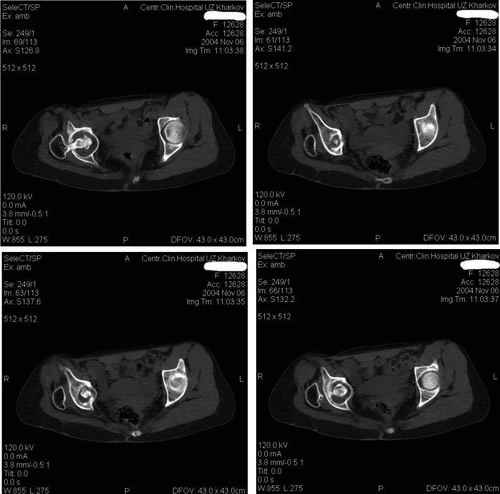

Уважаемые коллеги! Окажите, пожалуйста, консультативную помощь! Женщина 32 лет. Последствия перенесенного правостороннего гнойного коксита. Коксит явился следствием абсцесса правой паховой области развившегося после введения наркотиков в паховые сосуды. Наркотики не употребляет с 2000 года. Свищ закрылся год назад. В настоящее время в правой паховой области имеется рубец, спаянный с горизонтальной ветвью лобковой кости. Признаков воспаления нет. Нога не опорна из-за порочной установки. Вопрос: тотальное эндопротезирование или корригирующая остеотомия бедренной кости ? Заранее благодарю! С уважением,А.В.ВладзимирскийДонецкий НИИ травматологии и ортопедииДонецк, Украина